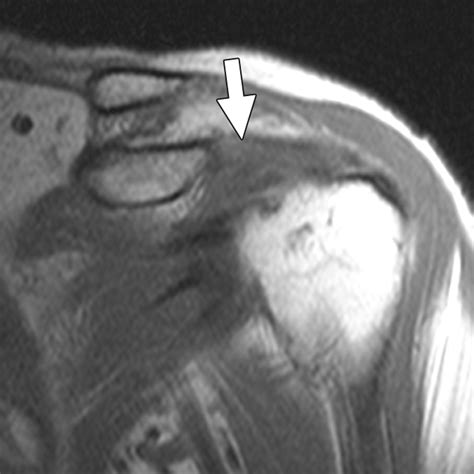

Magnetic Resonance Imaging (MRI) The gold standard for visualizing soft tissue, ligamentous thickening, and interval tears.

Magnetic Resonance Arthrography (MRA) Provides enhanced detail by injecting contrast into the joint, ideal for detecting minor labral or interval ligament tears.